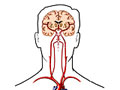

An angiogram of the head and neck is an X-ray test that uses a special dye and camera (fluoroscopy) to take pictures of the blood flow in the blood vessels of the head and neck. An angiogram of the neck (carotid angiogram) can be used to look at the large arteries in the neck that lead to the brain. An angiogram of the head (cerebral angiogram) can be used to look at the veins or the four arteries (four-vessel study) carrying blood to the brain.

During an angiogram, a thin, soft tube called a catheter is placed into a blood vessel in the groin or just above the elbow. The catheter is guided to the head and neck area. Then an iodine dye (contrast material) is injected into the vessel to make the area show clearly on the X-ray pictures. The angiogram pictures can be made into regular X-ray films or stored as digital pictures in a computer.

• A four-vessel study. The catheter is placed in each of the four arteries carrying blood to the head and neck (two carotid arteries and two vertebral arteries).

• An arch study. The catheter is pulled back from the head and neck area until the tip is at the large artery (aorta) where it leaves the heart. This study lets your doctor check the arteries where they branch off the aorta.